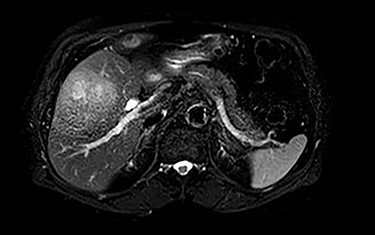

MRI demonstrated a 7.1 × 8.1 cm mass originating from the gallbladder that involved segments IVb, V, VI with areas of peripheral enhancement and central necrosis. Associated cholelithiasis was also noted. Figures 3–5 demonstrate the pertinent MRI findings.

MRI (axial view): 7.1 × 8.1 cm mass originating from the gallbladder involving segments IVb, V, VI with areas of peripheral enhancement and central necrosis.